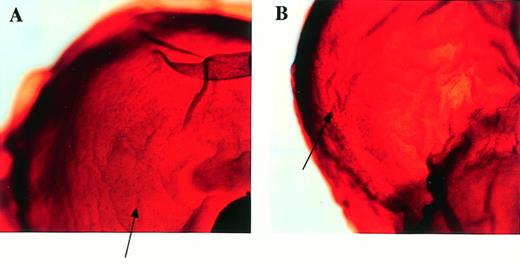

Fetal livers from Mll+/+, Mll+/mu, and Mllmu/mu littermates at E11.5 and E12.5 were examined histologically. Fetal liver cells, particularly hematopoietic cells, were slightly reduced in Mllmu/mu embryos compared with those in Mll+/+ and Mll+/mu littermates at E11.5 (Fig 3A and B). The decrease in hematopoietic cells was prominent in the livers of Mllmu/muembryos compared with those of Mll+/+ and Mll+/mu littermates at E12.5 (Fig 3C through F). In addition, the total number of cells in Mllmu/mu fetal livers was decreased at E12.5 in comparison with those of Mll+/+ and Mll+/mu littermates (Table 3). However, the appearance of fetal liver cells was similar among Mll+/+, Mll+/mu, and Mllmu/mu littermates in the liver stamp specimens stained with May-Grünwald/Giemsa. Erythroid, myeloid, and monocytic cells were present at various stages of differentiation in Mll+/+, Mll+/mu, and Mllmu/mu fetal livers (Fig 4A through D, Table 4). Megakaryocytes were also present in Mllmu/mu fetal livers (Fig 4E and F, Table 4). The presence of granulocytes and monocytes in Mllmu/mu fetal livers was also confirmed by fluorescence-activated cell sorter (FACS) analysis using anti-Mac1 and anti-Gr1 antibodies (Fig 5). We also confirmed the presence of macrophages in tissues of Mllmu/mu embryos by immunohistochemistry using the antimacrophage antibody F4/80 (Fig 6, see page 110). Further, we analyzed the components of peripheral blood at E12.5 and found mostly nucleated red blood cells, with few leukocytes and a few anucleated red blood cells derived from definitive erythropoiesis in fetal liver. These findings were similar among Mll+/+, Mll+/mu, and Mllmu/mu embryos (Fig 7, see page 115).

Histological examination of fetal livers. (A and B) Sections of fetal liver at E11.5 stained with HE (original magnification [OM] × 200). Hematopoietic cells in Mllmu/mu fetal liver were slightly decreased. (C through F) Sections of fetal liver at E12.5 stained with HE (OM × 100). The decrease of hematopoietic cells in Mllmu/mu was prominent. (A, C, and E) Mll+/+; (B, D, and F) Mllmu/mu.

Detection of macrophages in Mllmu/mu embryos by whole-mount immunohistochemistry using antimacrophage antibody F4/80. The heads of embryos at E12.5 are magnified (OM × 80). There are many F4/80+ cells (arrows). (A) Mll+/mu; (B) Mllmu/mu.